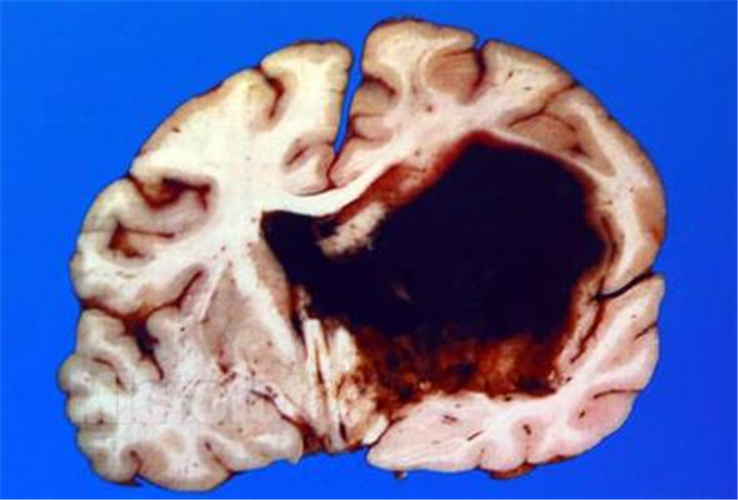

腦出血剖面